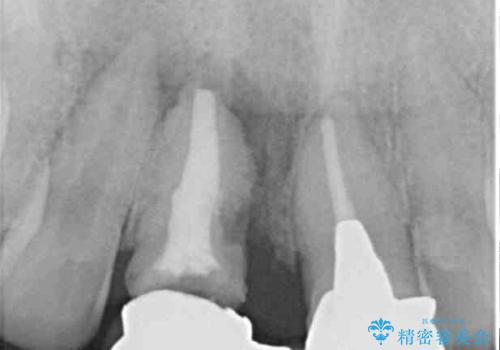

検査したところ、右前歯は抜歯が必要であったので、ブリッジを新製することとしました。

抜歯をすると歯肉が窪んでしまうので、傷口の治りを待って、歯肉移植を行うこととしました。

1歯は根管治療を行うことが必要と判断されたため、根管治療を実施することとしました。